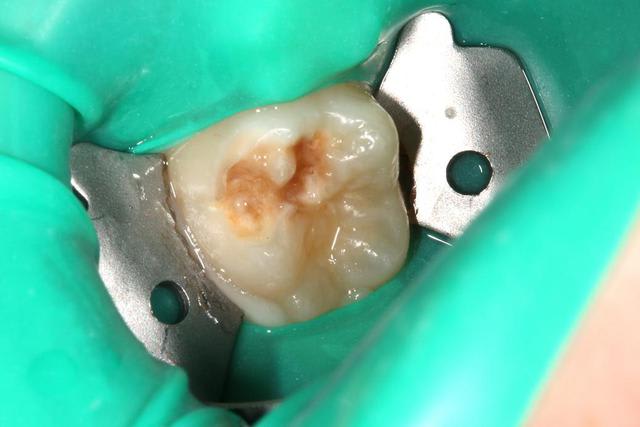

endo1_fye5ff.jpg

Voir le message contenant cette image